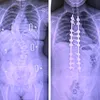

@thaisharris: We love good back brace mornings ☺️ hope you all have a great day!! ✨💚 #scoliosiswarrior #scoliosisawareness #raisinglittlepeople #MomsofTikTok

Maybe I would have liked my brace a lot more as a child if I would’ve decorated it my brace was plain and ugly and painful

the short hair suits her so much and I just wanted to say I had my spinal fusion 8 days ago